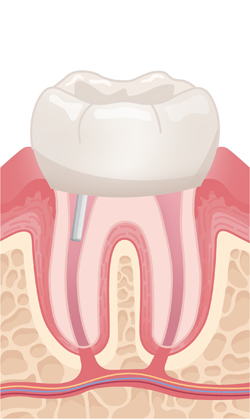

신경치료를 한다고해서 이미 죽은 조직을 살릴 수는 없지만 신경치료를 통해 통증을 없애주고 염증이 치아 뿌리를 싸고 있는 뼈 조직으로 퍼지는 것을 막아줍니다.

이처럼 신경치료는 치아를 뽑지않고 치아의 형태와 기능을 최대한으로 오랫동안 사용할 수 있도록 보존하는 치료입니다.

약해진 치아를 보호하기 위해 맞춤 제작된 크라운을 씌워 강도와 기능을 회복시키며, 장기적으로 안전하게 사용하도록 마무리합니다.